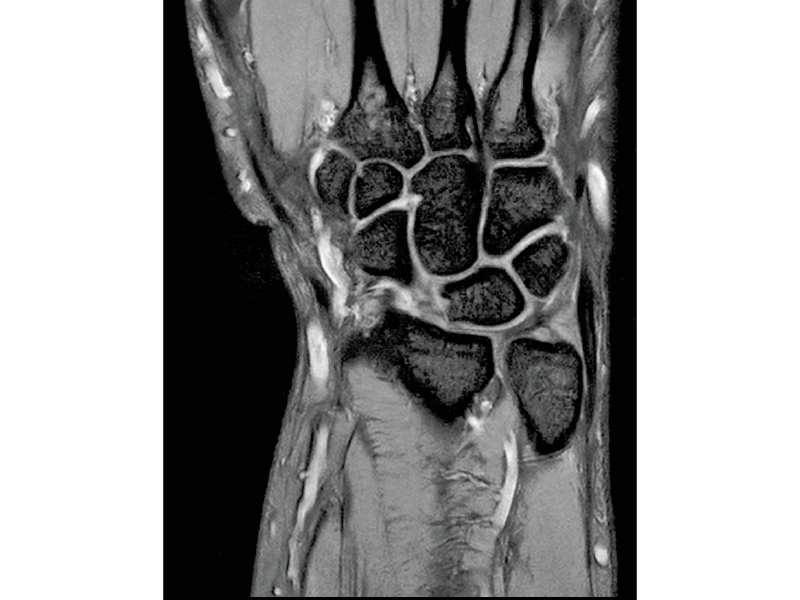

T2*WI Multi Echo,

0.38×0.38×2.0mm